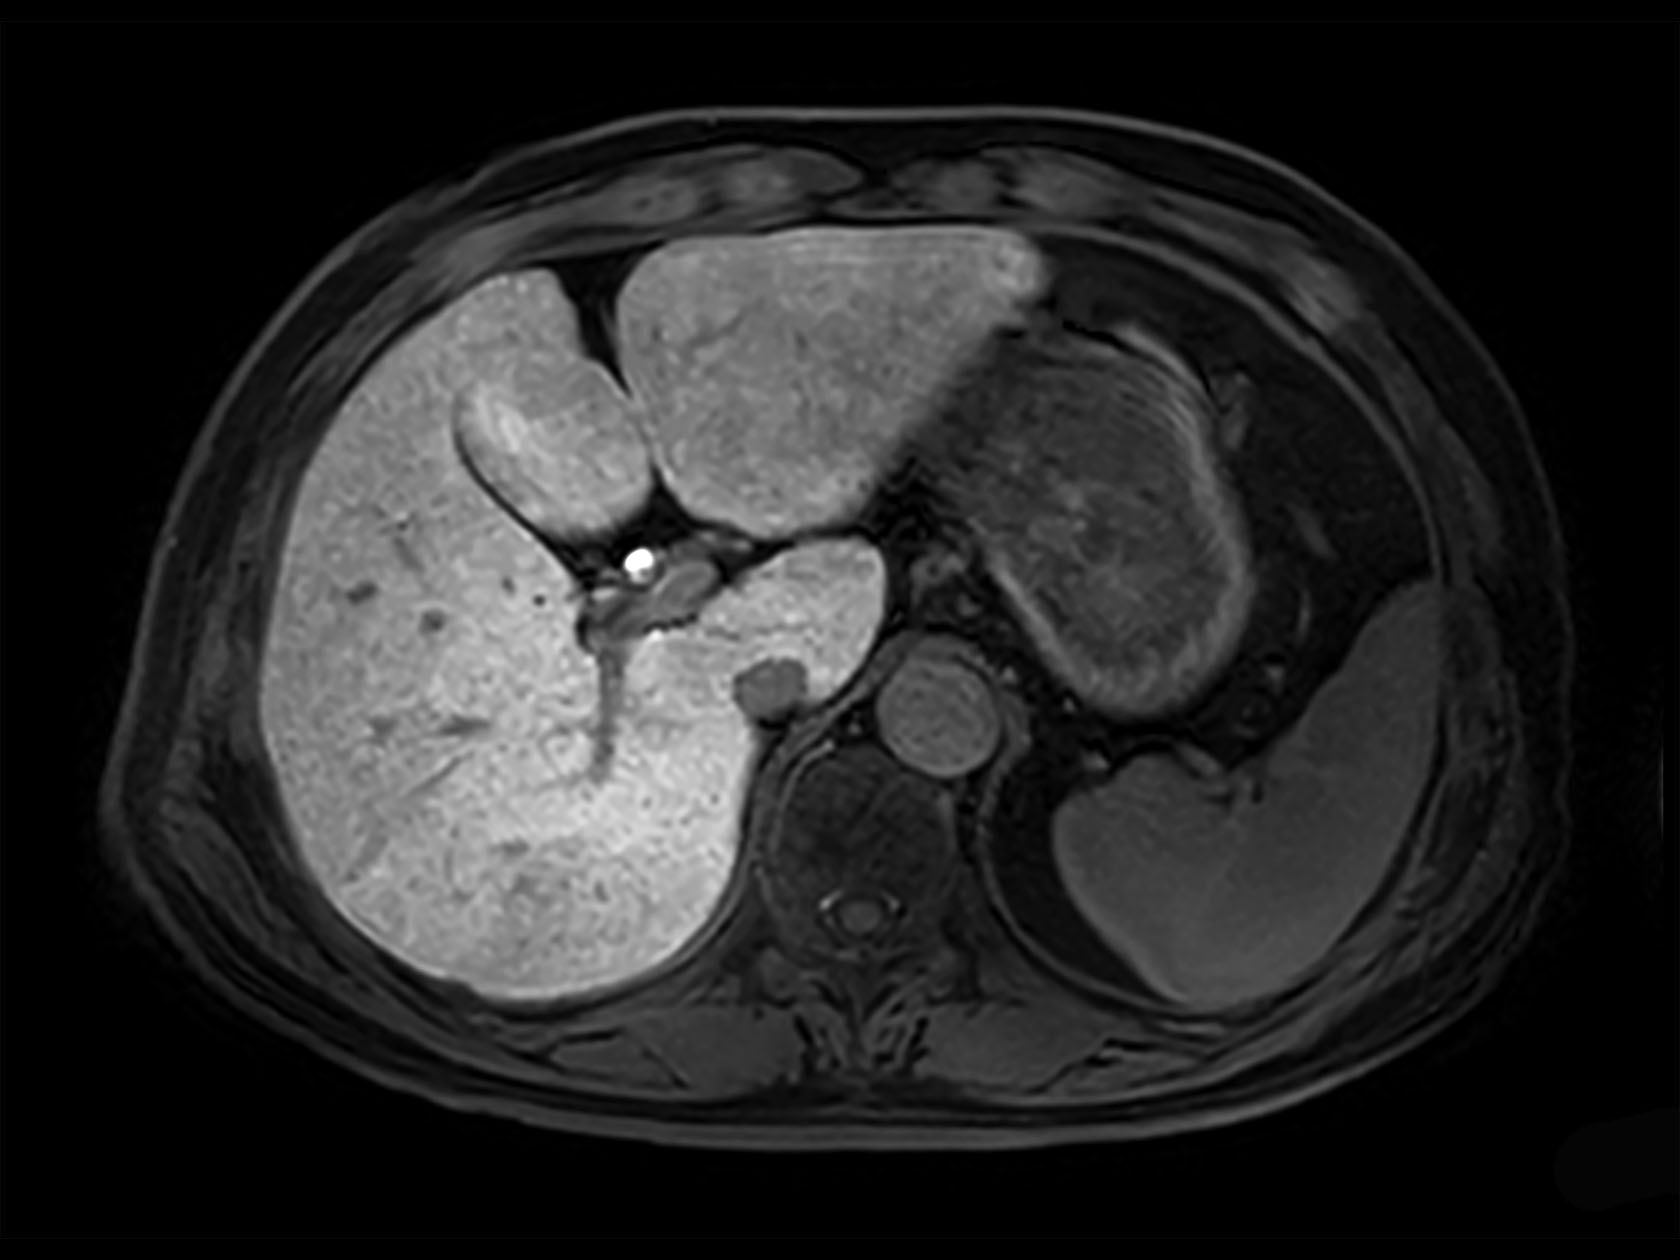

dyn mDIXON XD FFE  (post gado, venous phase)